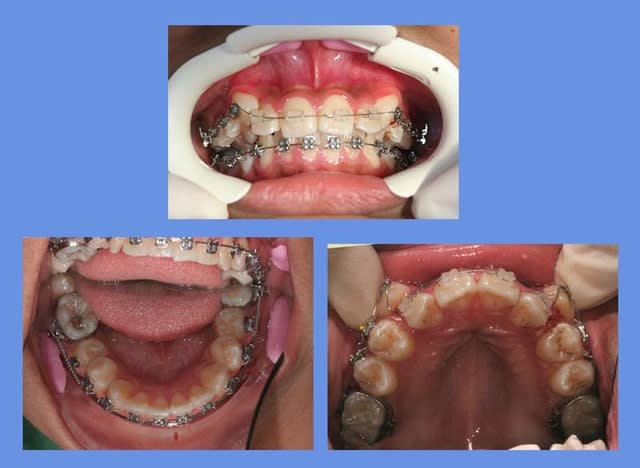

voici un cas d’incisives Inf. qui est une indication d’extraction selon les critères d’il y a 25